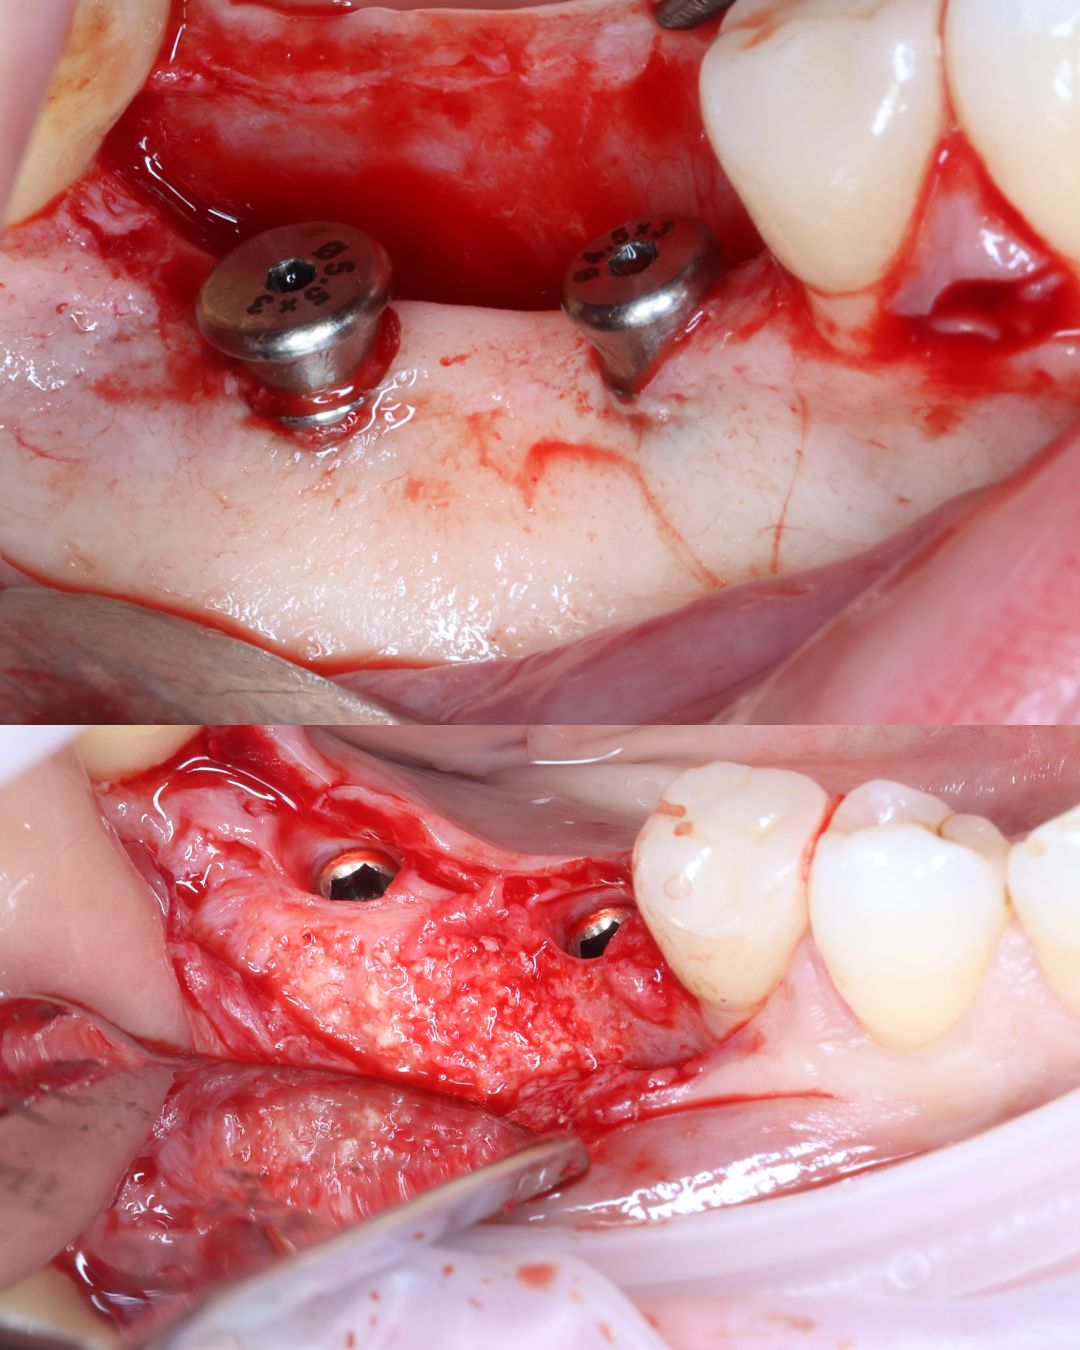

High Quality Surgical Recordings

Study high-quality surgical recordings that capture procedures step-by-step, allowing you to observe critical decision-making, tissue handling, and anatomical management in real clinical scenarios.

- GBR Using Tacks and Screw Fixation (Hands On)

- How to harvest autogenous bone safely and easily